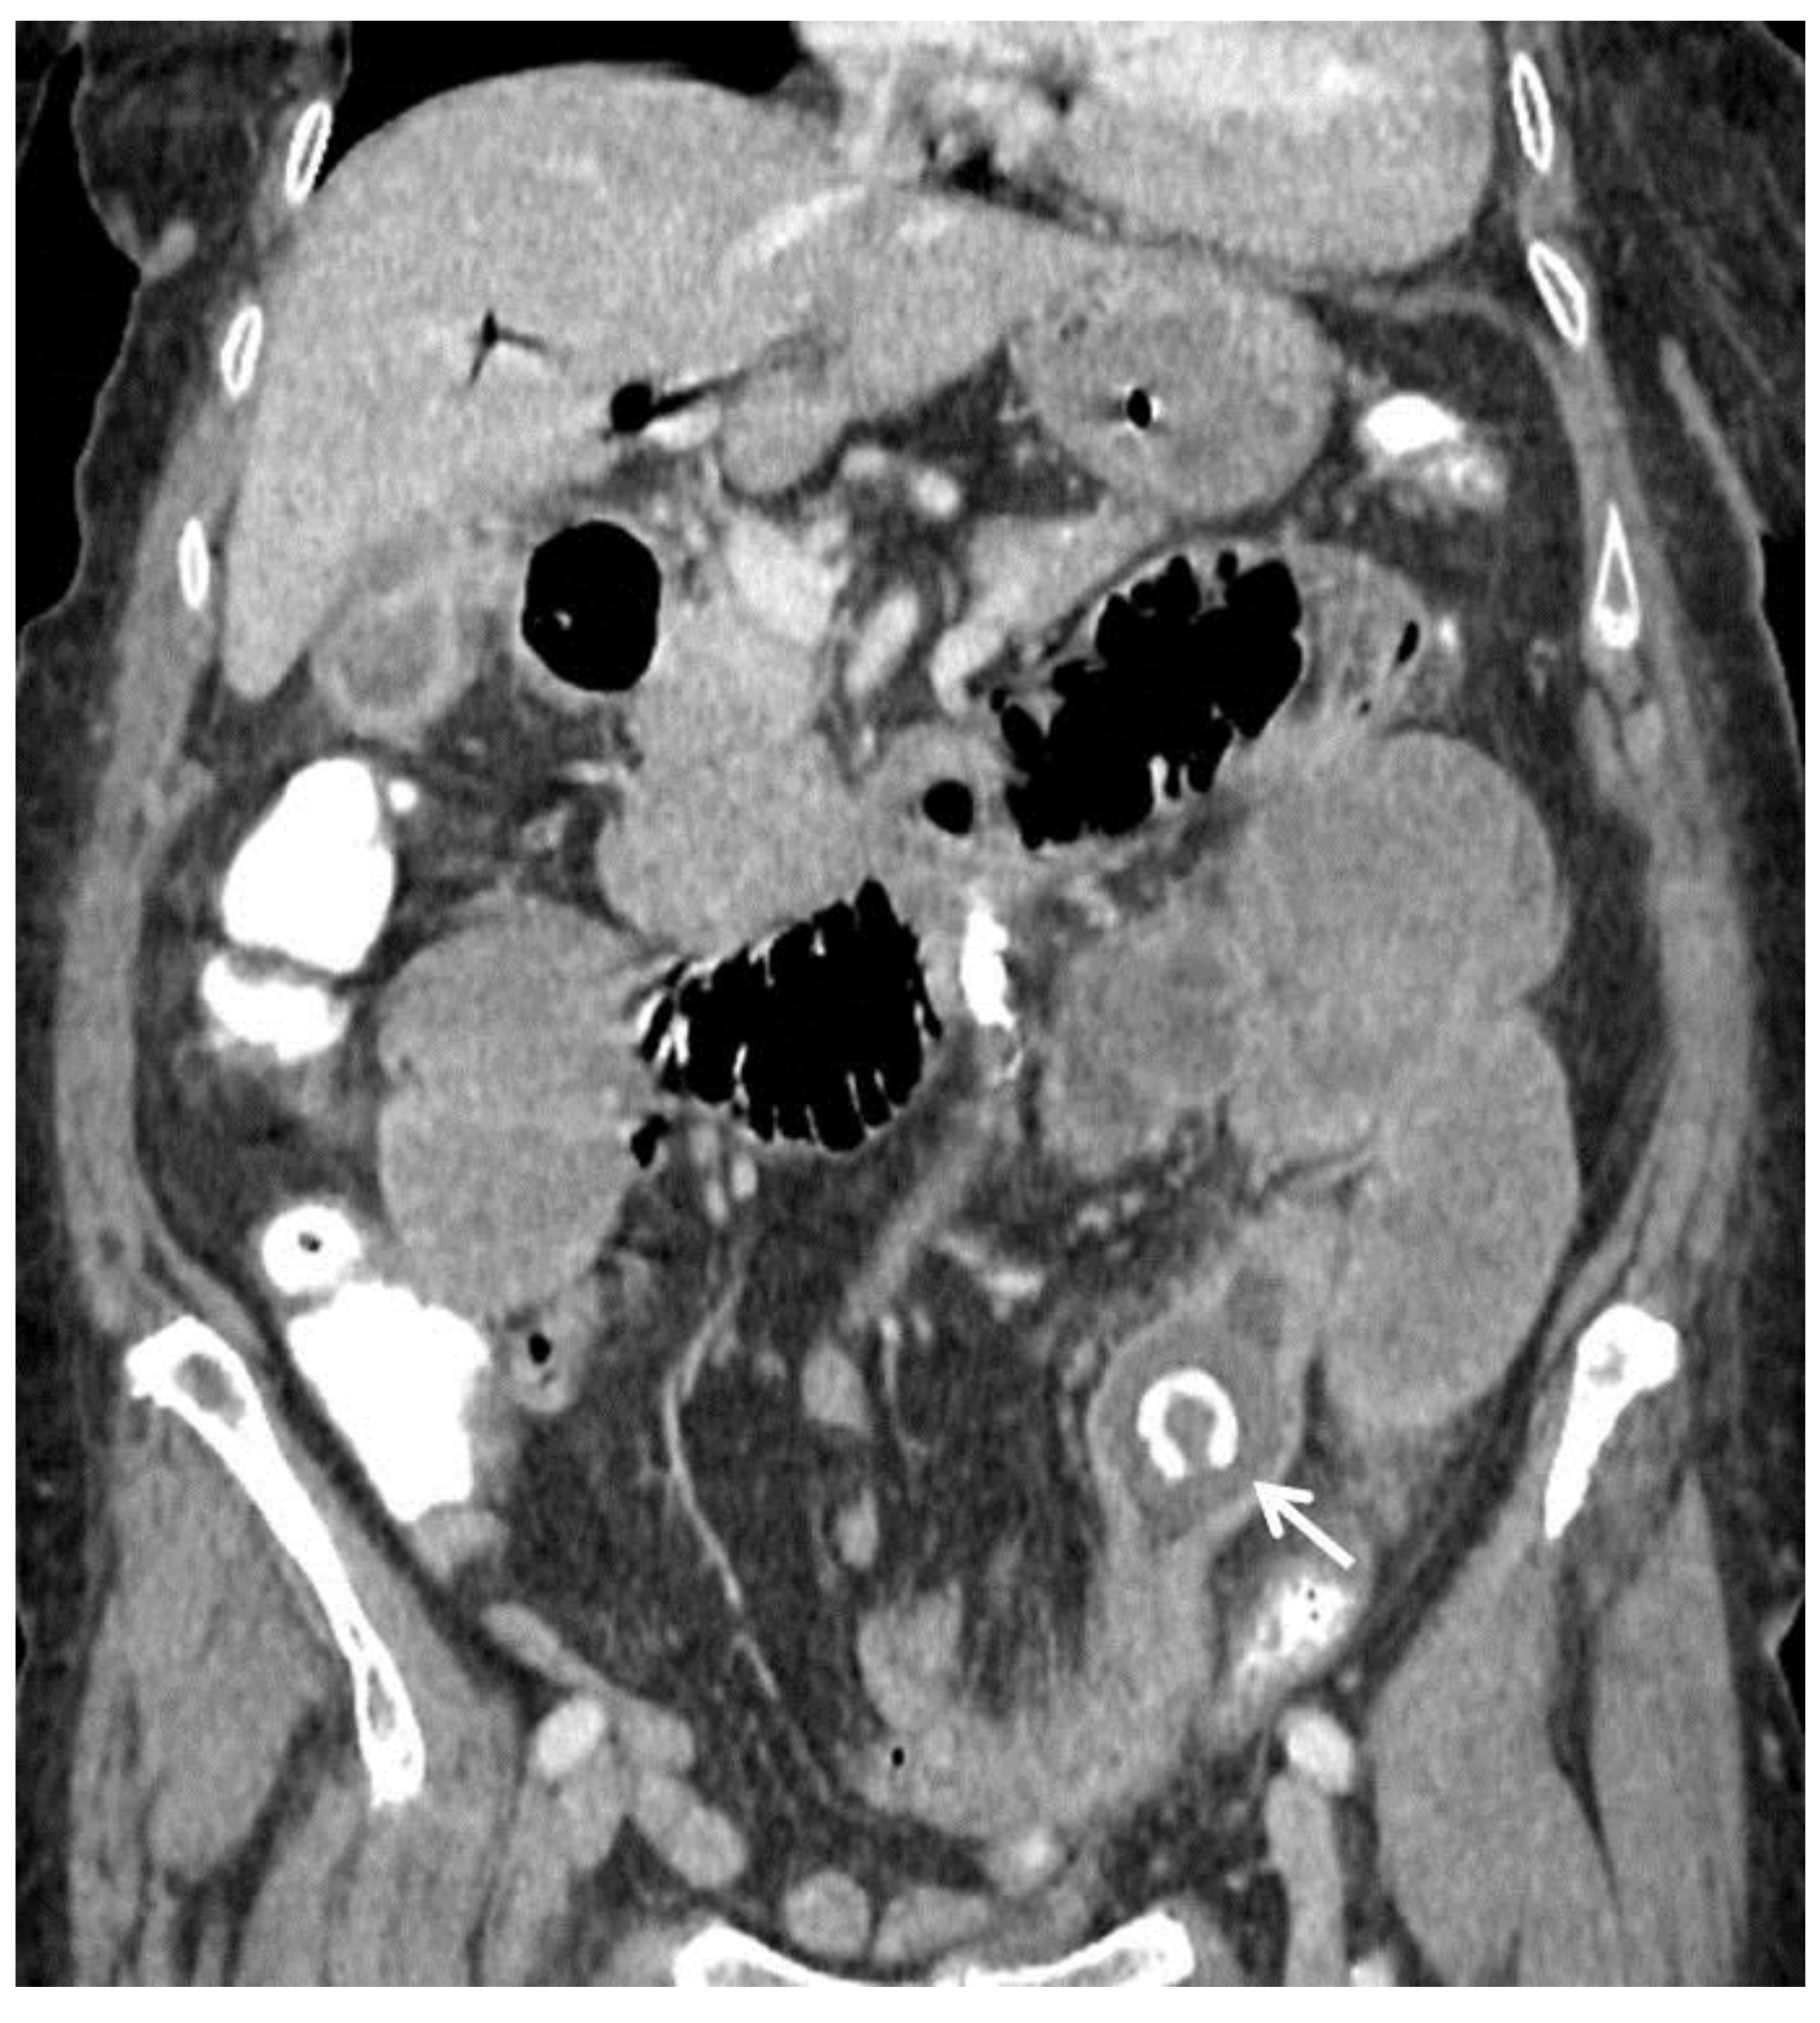

| F, 82 | 25 | III | Laparoscopically assisted enterolithotomy | 95 | Ileum | 3 × 3 cm | 3 | 14 | Good: recovery |

| F, 48 | 40 | III | Laparoscopically assisted enterolithotomy | 70 | Ileum | 3 × 4 cm | - | 10 | Good: recovery |

| F, 85 | 47 | IV | Laparoscopically assisted enterolithotomy | 60 | Ileum | 4 × 3 cm | 12 | 13 | Good: recovery |

| F, 69 | 12 | III | Colonoscopy | 115 | Sigmoid colon | 5 × 4 cm | - | 10 | Good: recovery |

| F, 87 | 2 | IV | Laparotomy with enterolithotomy | 35 | Jejunum | 4 × 3 cm | 5 | 7 | Poor: death |